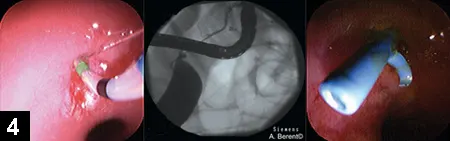

Figure 1. Endoscopic- and fluoroscopic-guided placement of a nasopharyngeal stent (circle) in a cat with a nasopharyngeal stenosis

Nasopharyngeal stenosis is a pathologic nasopharyngeal narrowing typically located caudal to the choanae, resulting in static inspiratory stertor. Nasopharyngeal stenosis can occur congenitally or secondary to an inflammatory condition (eg, aspiration, chronic rhinitis), surgery, trauma, or space-occupying lesion. Fixing the stenosis has traditionally involved surgery or serial balloon dilatation. Of note, although balloon dilatation is minimally invasive and uses interventional fluoroscopy and endoscopy, it can result in restricture within days to weeks. In the author’s experience, stenting (Figure 1) may allow more permanent fixation when balloon dilatation fails; results in both dogs and cats have been promising. Patients are usually released the same day as the procedure with antifibrotic doses of glucocorticoids (eg, prednisone 0.5 mg/kg q12h, tapered over 6–8 weeks) and antibiotics.